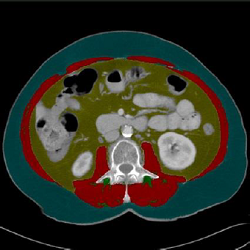

F1 (Grey)

For analyzing boundaries

between muscle and organs

F2 (Mixed)

Usually used for the actual process

of colouring/tagging tissues